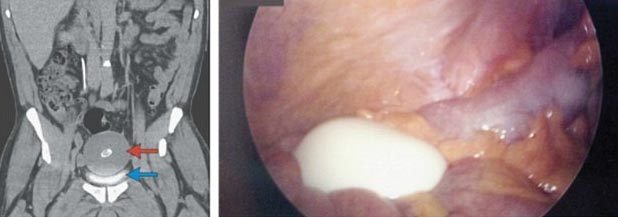

Tuy nhiên, khi tiến hành chụp cắt lớp vùng ổ bụng của bệnh nhân, các bác sĩ phát hiện một khối u "khủng" đang chèn ép bàng quang của ông. Một camera chuyên dụng tí hon được đưa vào bụng của bệnh nhân sau đó hé lộ, khối u "đặc, trơn nhẵn và có tính đàn hồi như cao su, đang trôi nổi tự do".

Kích thước của khối u được xác định lên tới 10cm chiều dài và khoảng 7,5 cm chiều rộng. Trọng lượng của nó đạt 220g, nặng hơn một quả cam cỡ trung bình.

Theo các chuyên gia, khối u trông giống một quả trứng luộc cỡ lớn này là một thể lỏng màng bụng. Nó được cho là hình thành khi túi thừa mạc nối hay bờm mỡ (các túi mỡ gói cuộn lại trong màng ruột) bị mở xoắn, trở nên tách rời và lỏng lẻo. Chúng sau đó biến đổi thành các khối u xơ và bị canxi hóa.

Các bác sĩ đã tiến hành nhuộm màu khối u bằng mực xanh để thấy rõ các lớp khác nhau của nó. Họ phát hiện, khối u gồm một lớp mô xơ, protein và chất xơ ở trung tâm. Bao quanh chúng là một vòng mô bị canxi hóa. Cấu trúc của khối u quả thực trông tương đối giống một quả trứng đã luộc chín với lòng trắng bao bọc lòng đỏ.